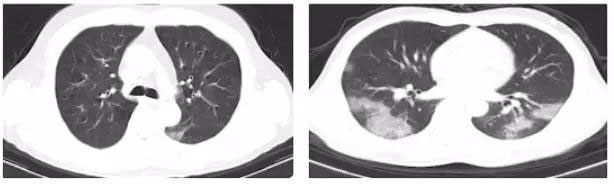

1. 部位特征

胸膜下,由单一病灶迅速扩展至双肺;

2. 基本病变

磨玻璃影,伴有间质增厚,血管增粗,可见铺路石征;

3. 受累情况

未受累的肺影像表现正常;

4. 少见改变

少数出现结节伴晕征,胸水;

5. 罕见表现

支气管改变,淋巴结增大不多见。